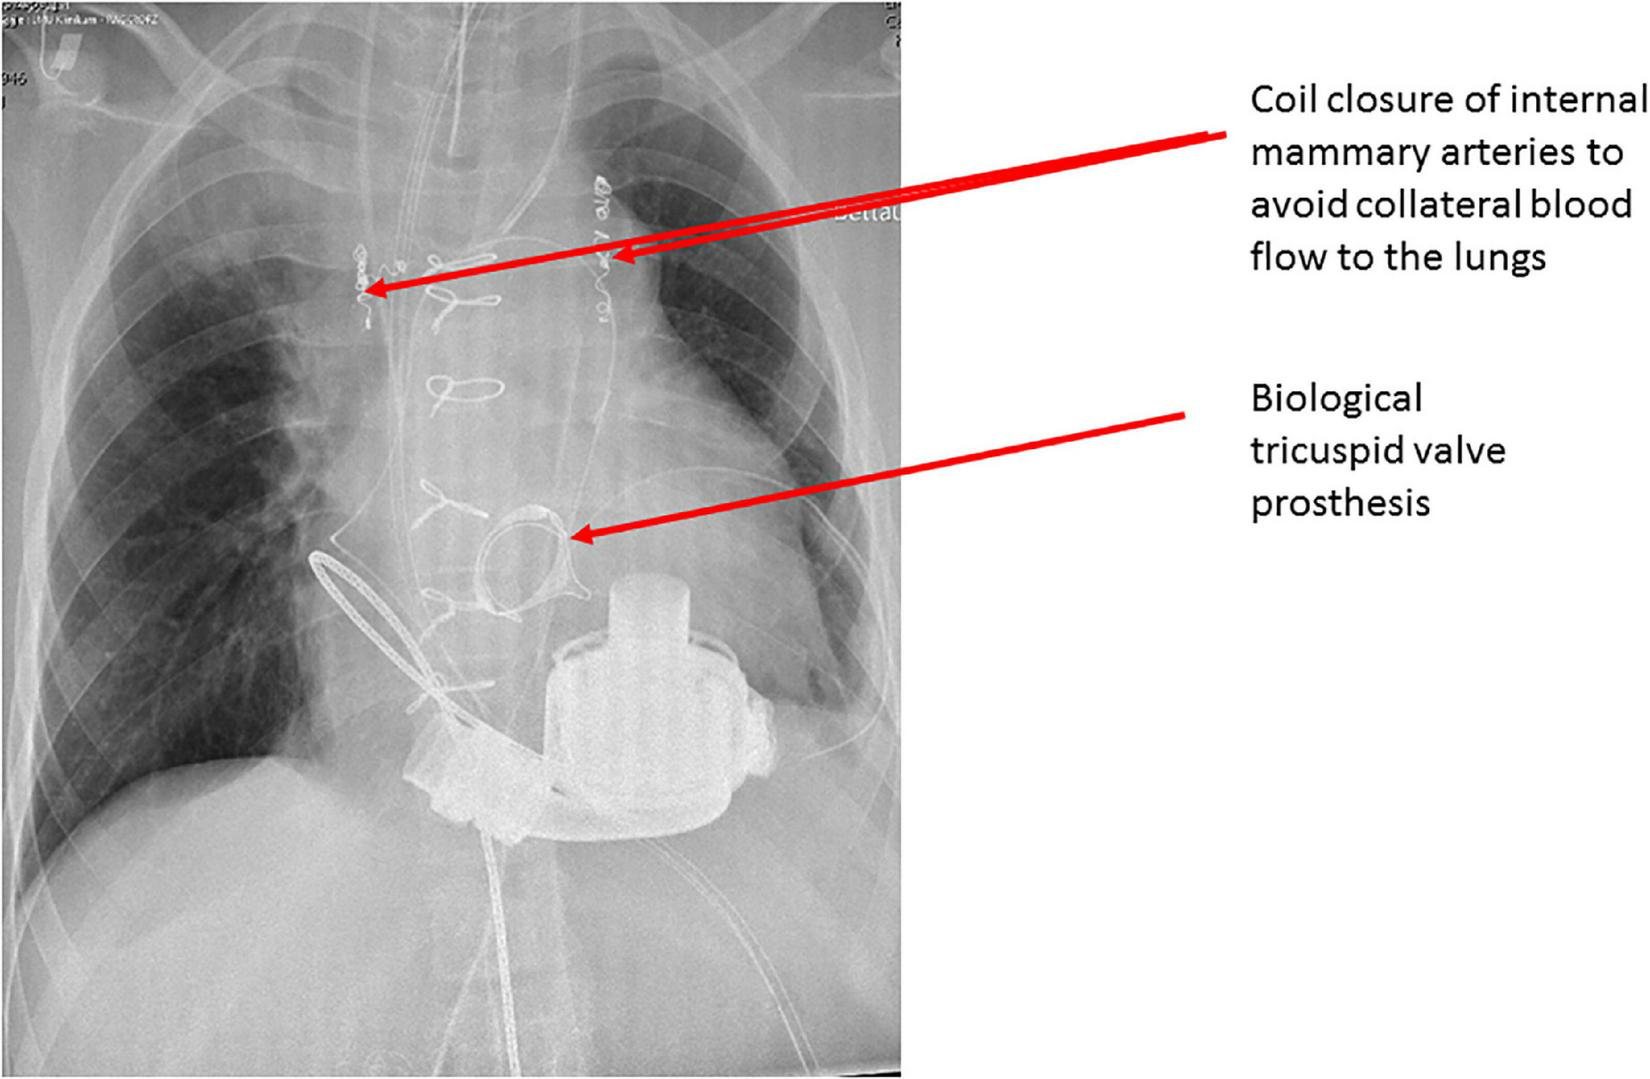

FIGURE 4

Postoperative chest x-ray showing adequate positioning of the Heart Mate 3 device in the right ventricle as well as the tricuspid valve bioprosthesis.

The patient was a 13-year-old male with HLHS who underwent Norwood procedure with a 5 mm Sano-shunt in the neonatal period. Bidirectional cavopulmonary anastomosis was performed at the age of 5 months, and the Fontan circulation was completed with an extracardiac non-fenestrated 18 mm Goretex conduit at the age of two years. At that time we also closed aorto-pulmonary collaterals to the right lung. Incipient reduction of exertional capacity was evident seven years after the total cavopulmonary anastomosis. By the age of 12, he suffered from symptoms of advanced heart failure (NYHA III; peak oxygen consumption of 11.8 ml/min/kg in cardiopulmonary stress testing). Echocardiography and magnetic resonance imaging revealed a high-grade tricuspid valve regurgitation due to severe annular dilation (60 mm) and a markedly reduced systemic ventricle ejection fraction of 36%. His last heart catheterization showed a mean pulmonary artery pressure of 16 mmHg, and a transpulmonary gradient of 4 mmHg with increased right ventricular end diastolic pressure of 12 mmHg, so elevated pulmonary vascular resistance was ruled out. There was no more significant collateral blood flow to the lungs at that time. He deteriorated and was admitted to our center in cardiogenic shock with hypotension and lactate acidosis peripheral veno-arterial extracorporeal life support (ECLS) was established using the femoral vessels. Tricuspid valve replacement (33 mm perimount) was performed on the 3rd day of ECLS support, which was continued postoperatively. Renal and hepatic functions were preserved while on ECLS support, but ECLS-weaning attempts were repeatedly unsuccessful. The decision was made to implant a HeartMate III (HM III) on the 9th day of ECLS treatment. The child was 45 kg and 165 cm which resulted in a body surface area of 1.43 m2. Surgical access was impaired due to extensive adhesions from previous procedures. ECLS was switched to cardiopulmonary bypass via the femoral vessels. The HM III was placed in the systemic—anatomically—right ventricle. Therefore, the sewing ring was enhanced with four layers of pledgets (Figures 1, 2) to reduce protrusion into the ventricular cavity as previously suggested for right sided VAD placement (5). Right-ventricular myocardial trabeculae, chords and parts of the papillary muscles of the tricuspid valve were resected to avoid inflow cannula obstruction. This was facilitated by the already implanted tricuspid valve bioprosthesis (Figures 3, 4). The modified sewing cuff was fixated with 8 interrupted pledgeted sutures. The outflow graft was anastomosed to the ascending aorta with 4-0 Prolene suture. Bypass time was 160 min. After weaning from cardiopulmonary bypass, the ventricular assist device (VAD) was gradually set at 5,800 rpm, reaching a flow of 4.5 L/min with a power consumption of 5.3 Watt. In the immediate postoperative period the patient was supported with inotropes and inhaled nitric oxide. The patient was extubated on the 4th postoperative day. A single run of renal replacement therapy was necessary on postoperative day 3. End-organ parameters were within normal range 3 weeks after VAD implantation. The postoperative course was complicated by bleeding events (hemothorax and GI-bleeding from esophageal varices). Mass transfusion was necessary during that period. After bleeding issues had been resolved, anticoagulation was started with heparine (target PTT = 60 s) and later was switched to Vitamin-K-antagonists Aspirine was not started until 6 weeks after surgery due to the GI bleeding. Additionally, impaired wound healing without evident infection could be observed at the driveline exit site. He was discharged from the hospital in good clinical condition on postoperative day 69. Logfiles remained unremarkable for low-flow or suction events. Evaluation for heart transplantation is currently ongoing.